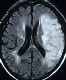

脳動脈の狭窄

全ての検査を終えると、医師から 一過性脳虚血発作 ( いっかせい のうきょけつ ほっさ、 T I A 、Transient Ischemic Attack ) と診断されました。さらに今回の発作とは関係ないが M R I 検査の結果から脳底動脈に狭窄 ( きょうさく、狭い部分 ) があり、 脳梗塞 ( のうこうそく ) 発症の可能性があるので 、ただちに入院するようにいわれました。上の M R I 画像は私のものです。